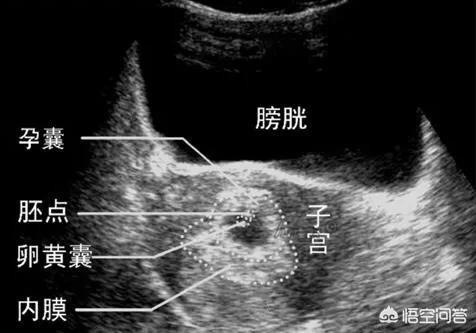

孕早期B超检查

孕8-9周左右,建议大家都做一次B超检查,此时可以清晰的看到胚胎发育情况,孕囊,胎心胎芽,排除宫外孕、葡萄胎、胎儿停育,确认胎儿数量胎儿宫内健康发育。